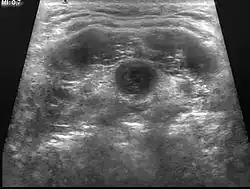

Ultrasound image of thyroglossal duct cyst

Diagnosis of a thyroglossal duct cyst requires a medical professional, and is usually done by a physical examination. It is important to identify whether or not the thyroglossal cyst contains any thyroid tissue, as it can define the degree of cyst that is being dealt with.[1]

Ultrasound Image capture of the degree of mass and its surrounding tissues.